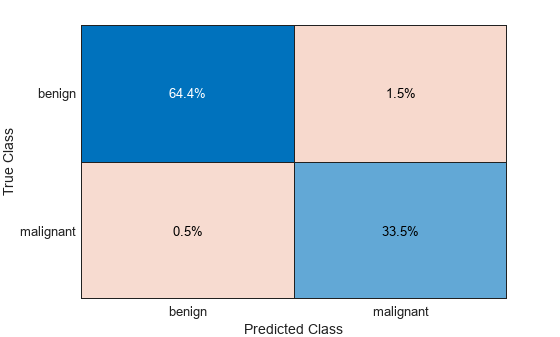

Evaluate Classification Accuracy

Compute the accuracy of the predicted labels from the confusion matrix.

confusionMatrix = confusionmat(labelsTest,predictedLabelsTest)

confusionMatrix = 2×2

125 3

1 65

accuracy = sum(diag(confusionMatrix))/sum(confusionMatrix,"all")accuracy = 0.9794

Create a normalized confusion matrix chart from the true labels labelsTest and the predicted labels predictedLabelsTest.

figure

confusionchart(labelsTest,predictedLabelsTest,Normalization="total-normalized")